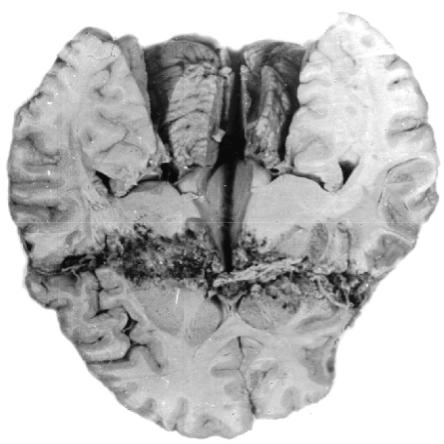

Сквозные ранения имеют входное и выходное отверстия. В зависимости от

хода и направления раневого канала различают сегментарные и диаметральные ранения. Сегментарными называют сквозные ранения, при которых раневой ка- нал проходит через полость черепа, поражая две соседние доли мозга. При диаметральных ранениях раневой канал проходит по диаметру, поражает оба полу- шария, нередко стволовые отделы, а также желудочковую систему мозга (рис. 57).

Рис. 57. Макропрепа-

рат головного мозга с диаметральным пуле- вым ранением: раневой канал с травматиче-

ским некрозом ткани головного мозга

Форма раневого канала при сквозных ранениях черепа может быть щеле- видной, сигарообразной, с воронкообразными расширениями в области входного

и выходного отверстий или в виде усеченного конуса с расширением в выходной части. Сквозные ранения черепа сопровождаются, как правило, обширными по- вреждениями ткани мозга, что определяет исключительную тяжесть таких ране- ний, нередко приводящих пострадавших к смерти непосредственно на поле боя.